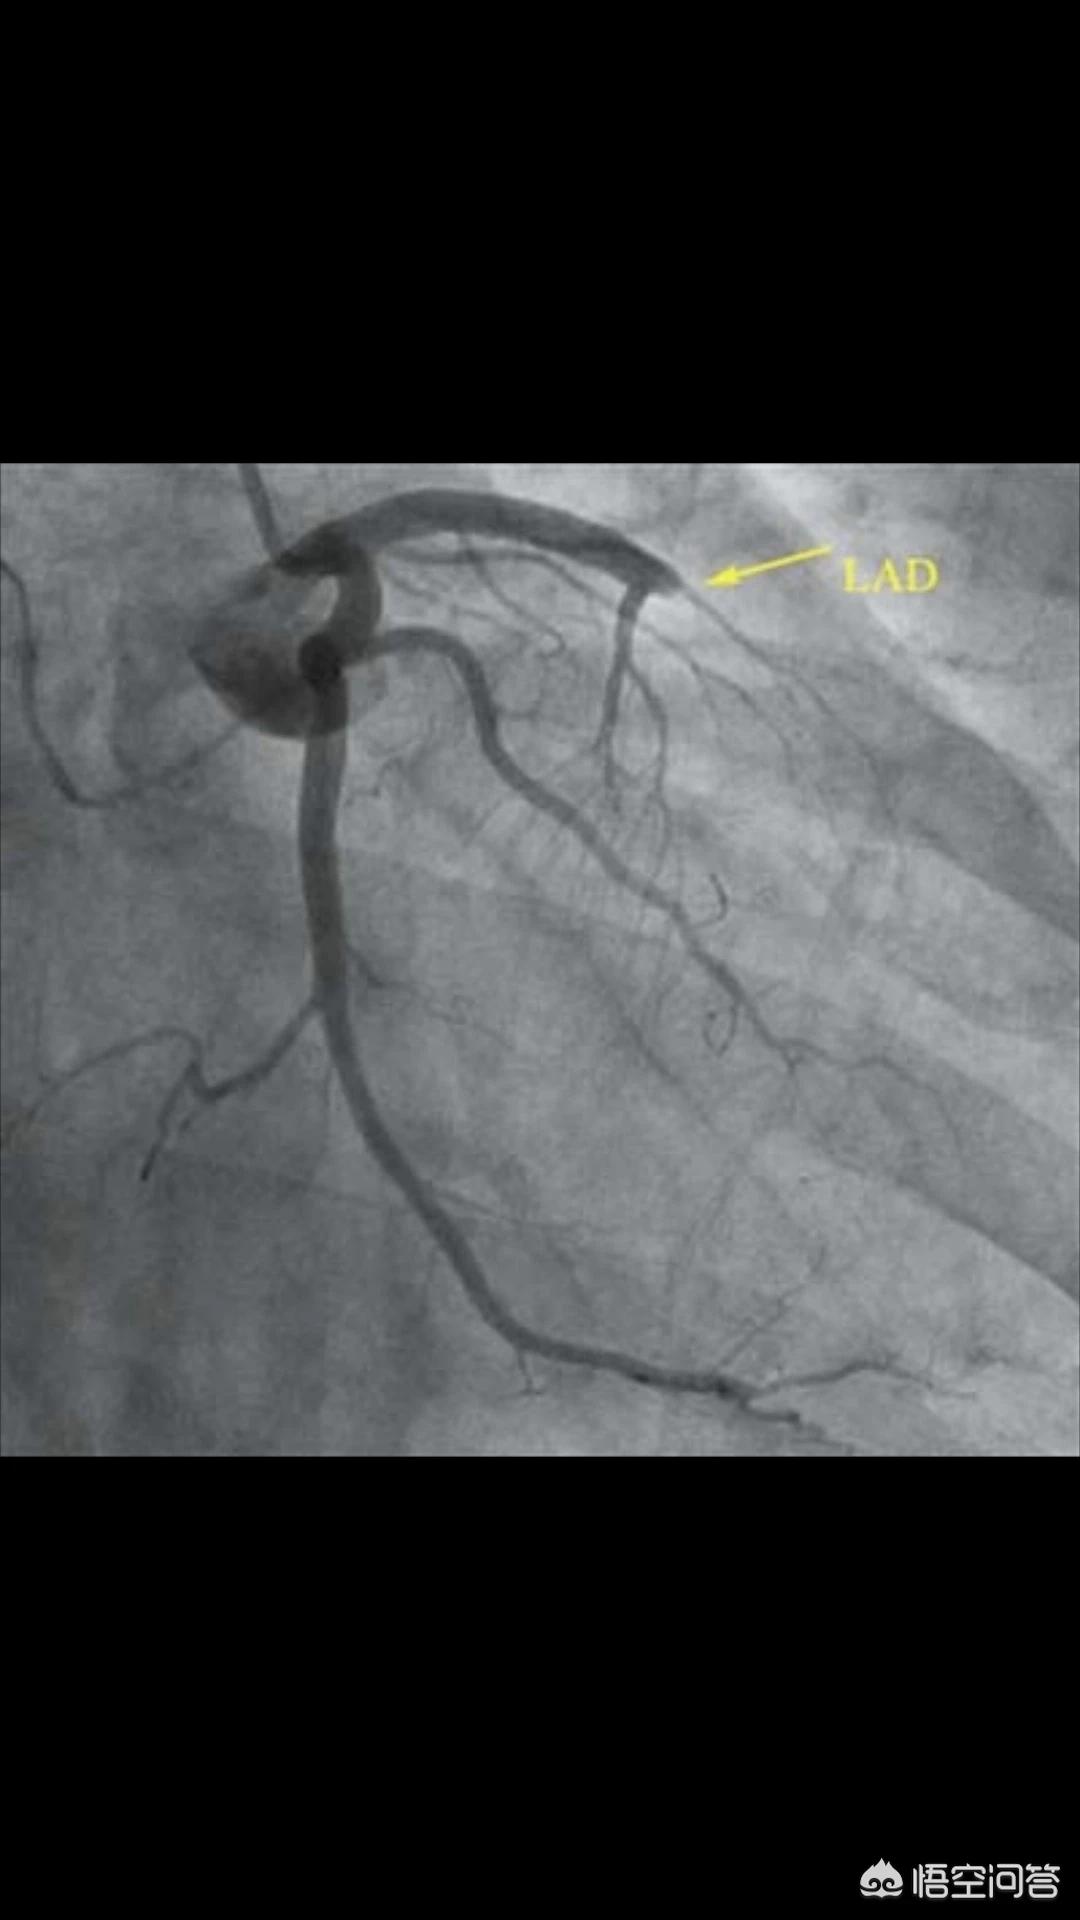

我们先假设堵死的时间相同,只是堵塞部位不同,那么三个血管相对来说,前降支最大,风险最高,死亡率最高;右冠和回旋支相对要风险低一些。也就是堵了前降支心脏不能正常运转可能性大,堵了别的两个相对会正常运转。

(前降支堵塞)

但这里面还有一个问题,堵在血管根部的还是末梢,堵在根本都会有生命危险,堵在末梢,即使在前降支也不会影响正常运转。还有就是特殊性,每个人血管大小不一样,并不是每个人前降支都最大,供血都最多。